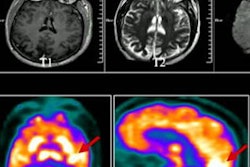

VIENNA - How does a professor of population imaging spend her day? And what makes Erasmus MC in Rotterdam, the Netherlands, such a special place to work? Neuroradiologist Dr. Meike Vernooij, PhD, addressed these and other questions in an interview at ECR 2023.

Dr. Meike Vernooij, chair of the European Society of Neuroradiology's Diagnostic Neuroradiology subspecialty committee, speaks about her latest research studies with Stephen Wellman. Video produced by Christof.G.Pelz | GRAFIFANT Creation | www.grafifant.at | 2023